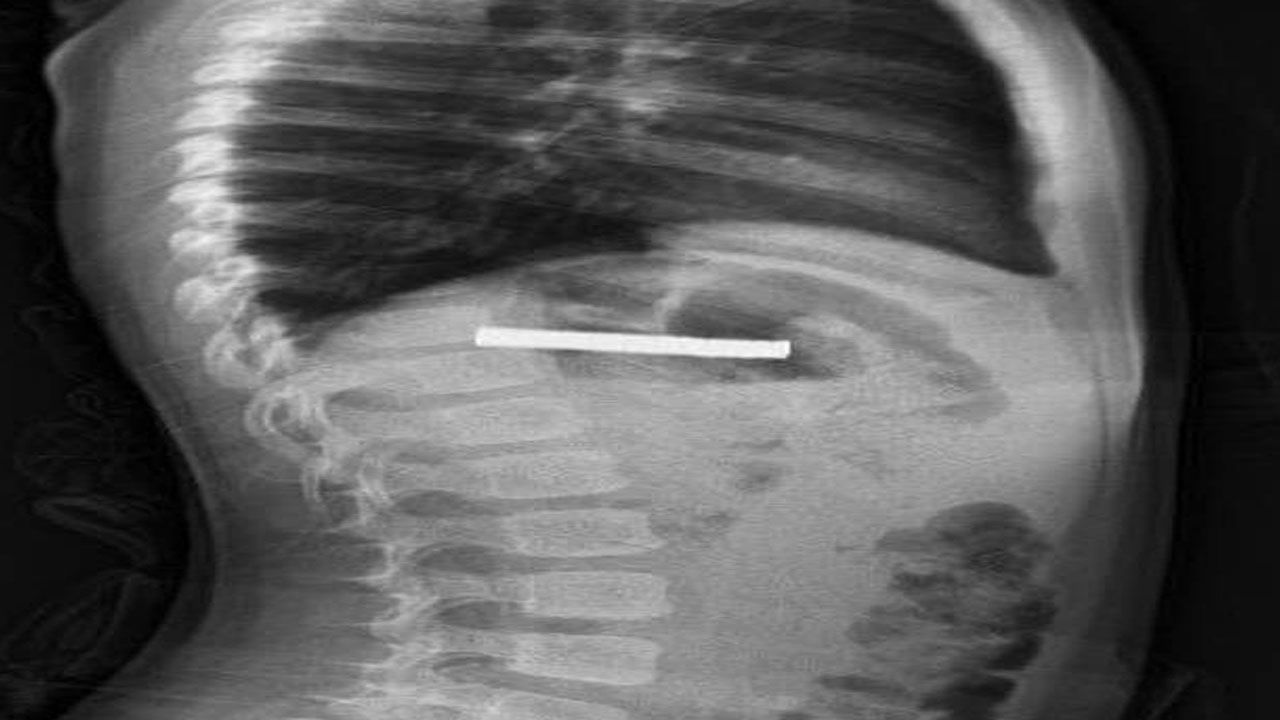

Edinilen bilgiye göre, Erzurum’da bir çocuk evde bulunan 19 tane mıknatısı yuttu. Çocuğun rahatsızlanması sonucu durumu öğrenen aile hastaneye başvurdu. Daha sonra çocuk Elazığ’a sevk edildi. Fırat Üniversitesi Çocuk Gastroenteroloji Hepatoloji ve Beslenme Bilim Dalı Başkanı Prof. Dr. Yaşar Doğan, çocuk hastanın yemek borusuna yapışmış 19 mıknatısı endoskopik yöntemle çıkardı.

Mıknatıslar uzun süre yemek borusunda takılı kaldığı için yemek borusu ve mide girişinde zedelenmeler olurken, çocuğun sağlık durumunun iyi olduğu ve taburcu edildiği öğrenildi.